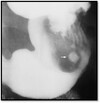

What pathology is shown here?

Intussusception